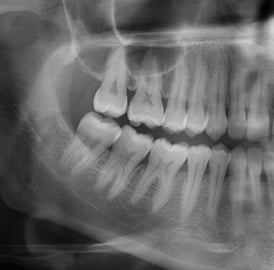

Je réaliserai tous les examens nécessaires (examen clinique, radiographies 2D et 3D, empreinte numérique, photographies…) afin d’établir un diagnostic précis

Je réaliserai tous les examens nécessaires (examen clinique, radiographies 2D et 3D) afin d’établir un diagnostic précis